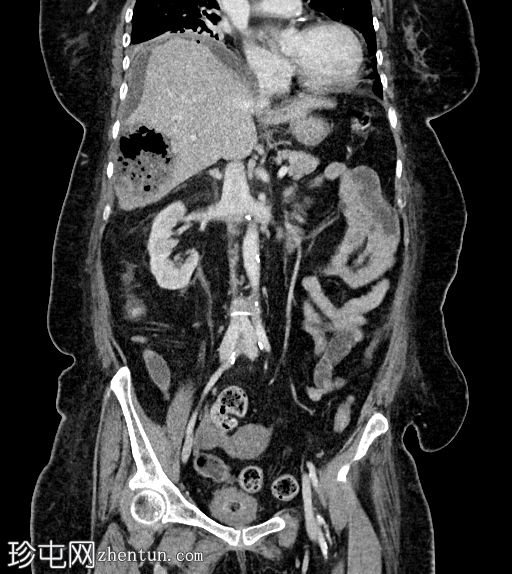

矢状位增强(C+)门静脉期

静脉期

8.jpg

肝段 6 和 7 可见多房性积液,呈环状强化

积液内可见多个气体腔

破入肝包膜下间隙,可见肝包膜下积液及气体腔

壁层腹膜与前腹壁之间可见另一局灶性积液

肝段 7 的肝内胆管局灶性扩张(0.3cm),内含气体腔

其他肝内胆管和肝外胆管均正常

胆囊缺失,可能由于既往胆囊切除术所致

无游离液体。

双侧肾皮质囊肿

轻度右侧胸腔积液伴邻近肺不张